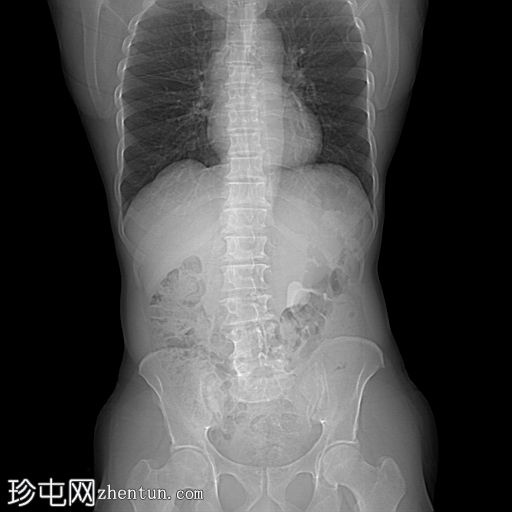

轴位

非增强

非增强CT KUB显示:

左肾盂内可见一高密度结石,压迫肾盂输尿管连接处。

下肾盏内可见一小结石

未见明显反流、肾盂肾盏扩张或肾周脂肪浸润

输尿管或膀胱内未见明显结石